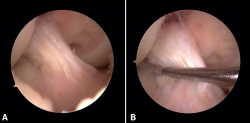

En ambos pacientes se realizó anestesia raquídea para realizar la cirugía y se utilizó manguito de isquemia a nivel del muslo. Se colocó al paciente en decúbito supino, utilizando un soporte en U en el tercio distal del muslo para la fijación de la extremidad. Se realizaron los portales artroscópicos habituales anterolateral y anteromedial, objetivando en la exploración diagnóstica de la rodilla la presencia de un ganglión localizado en el fascículo posterolateral del LCA (Figura 3) que, cuando se realizaban los movimientos de flexión y en posición de cuatro, se pinzaba en el espacio articular tibiofemoral externo. Para realizar la resección artroscópica del quiste se colocó al paciente en la posición “de cuatro”, facilitando la diferenciación anatómica de los fascículos anteromedial y posterolateral del LCA, tal y como proponen Hopper G et al.(4). Se realizó la disección y exéresis cuidadosa del quiste con una pinza basket, un terminal shaver de 4 mm y un terminal de ablación por radiofrecuencia (Figura 4). Al finalizar la resección del quiste, se realizó una nueva exploración dinámica de la rodilla, donde se evidenció la ausencia de pinzamiento entre el LCA, el cóndilo femoral y el platillo tibial lateral, a la vez que se comprobó la estabilidad del remanente del LCA (Figura 5).

Figura 4. Visión artroscópica desde el portal anterolateral. Se introduce a través del portal anteromedial el instrumental. A: inicio del desbridamiento del quiste con un basket artroscópico; B: se continúa el desbridamiento del quiste con un shaver de 4 mm respetando las fibras del ligamento cruzado anterior sano.